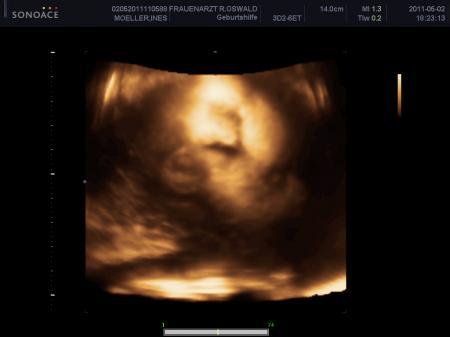

Bin etwas enttäuscht, es war sehr schwer die beiden Mädels zu schallen, sie waren sehr aktiv und haben sich die ganze Zeit gegenseitig getreten Habe aber ein paar Bildchen mitbekommen, und darf in 2 Wochen nochmal wiederkommen Hier einmal Zoe die ganz müüddee ist

Bild zu Zurück vom 3D;) - Forum für August - Mamis